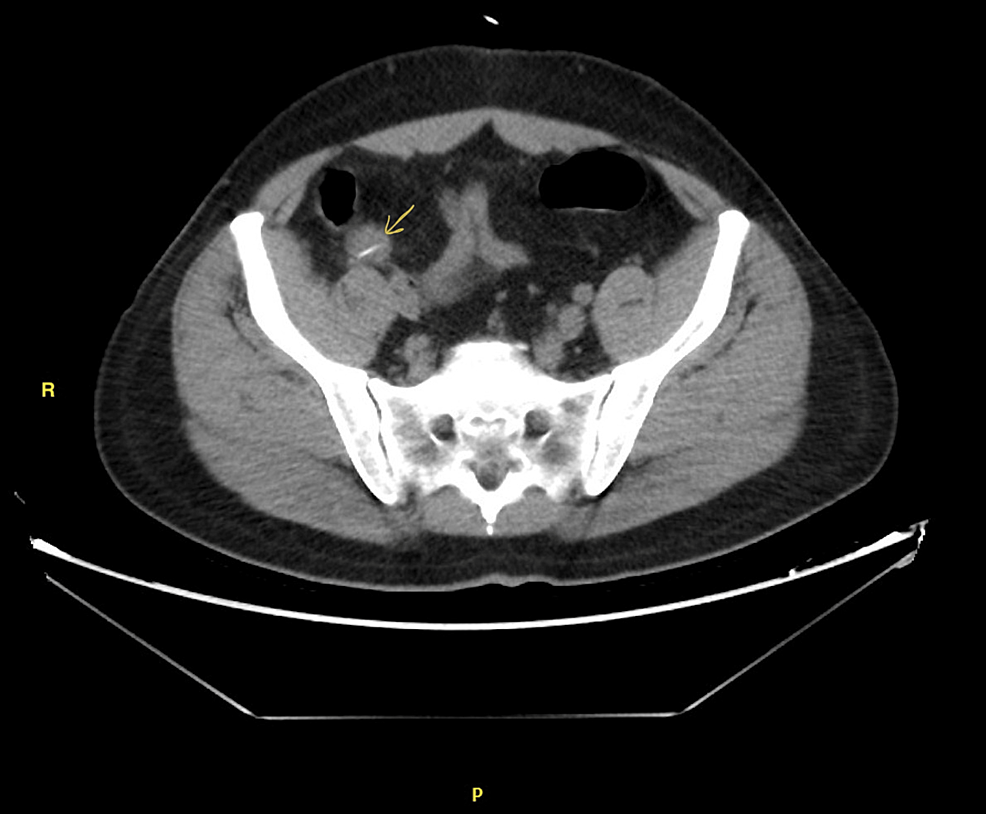

Abdominal CT bowel perforation • LITFL • Radiology Library Causes Of Bowel Perforation An overview of the clinical features, diagnosis, and management of the patient with alimentary tract perforation is reviewed here. The contents in your colon can leak out through the hole caused by a perforated bowel. There are three main causes of a perforated bowel: The most common form of bowel perforation trauma is an accidental injury to the. It can. Causes Of Bowel Perforation.

Abdominal CT bowel perforation • LITFL • Radiology Library Causes Of Bowel Perforation There are three main causes of a perforated bowel: Gastrointestinal perforation (gp) occurs when a hole forms all the way through the stomach, large bowel, or small intestine. This can cause bleeding, as well as a painful and serious infection. This condition can easily develop into serious. Bowel perforation results from insult or injury to the mucosa of the bowel. Causes Of Bowel Perforation.

Abdominal CT bowel perforation • LITFL • Radiology Library Causes Of Bowel Perforation It can be caused by several different conditions,. The most common form of bowel perforation trauma is an accidental injury to the. An overview of the clinical features, diagnosis, and management of the patient with alimentary tract perforation is reviewed here. Intestinal perforation, defined as a loss of continuity of the bowel wall, is a potentially devastating complication that may. Causes Of Bowel Perforation.